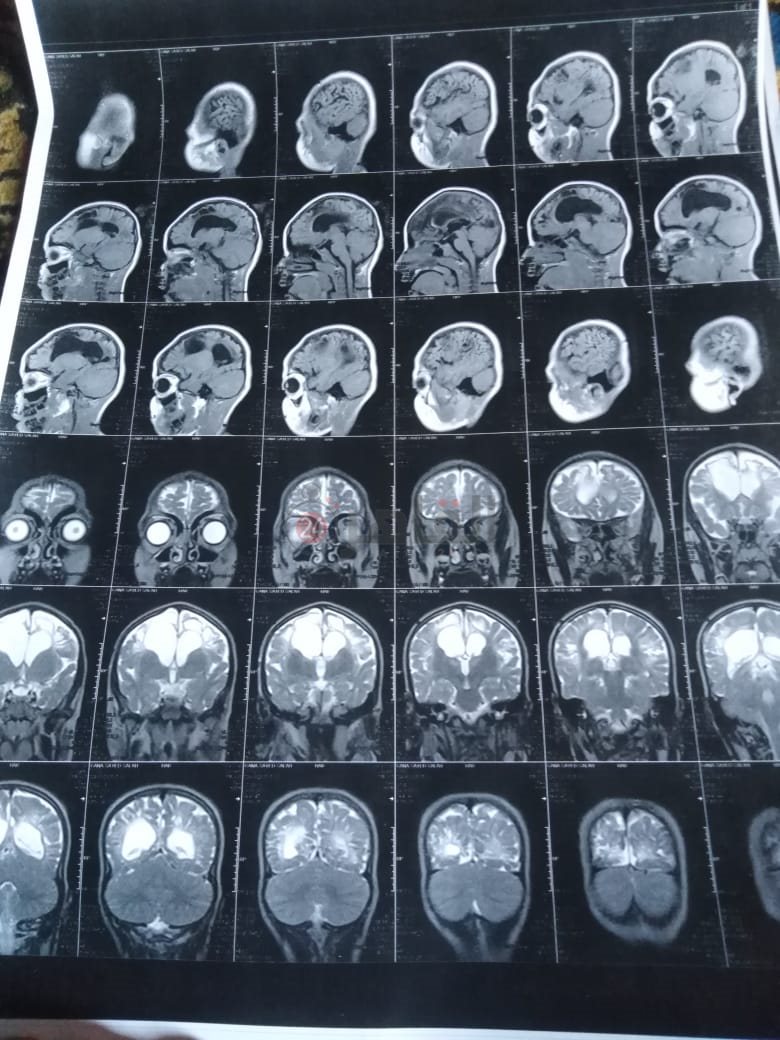

من جانبه، قال صلاح سيد، والد الطفلة جنى صلاح، إن ابنته تعاني من ضمور في المخ منذ ولادتها، نتيجة خطأ طبي، أدى إلى نقص كبير في الأكسجين لديها.

وتابع: "مكنتش بتتحرك خالص، وجسمها طري، روحت كشفت عليها، وعملت أشعة وتحاليل كتير، أتأكدنا إصابتها بضمور في المخ"، مضيفًا:" مش بتعرف تأكل احنا اللي بنأكلها، هي عقلها كويس لكن مش بتتحرك ولا تتكلم".